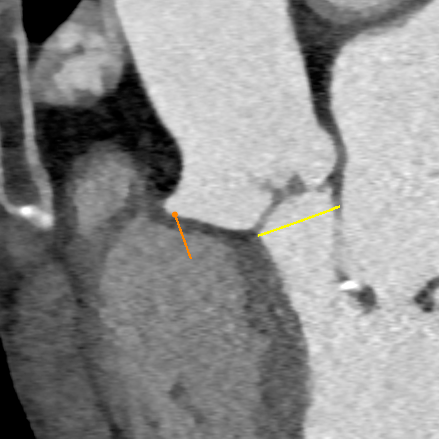

CT测量

主动脉根部CT

瓣环平均直径:

22mm

左室流出道平均直径:

23.3mm

窦宽:32/30/31mm

横位心:48°

左冠开口高度:

13.5mm

右冠开口高度:

10mm

入路情况